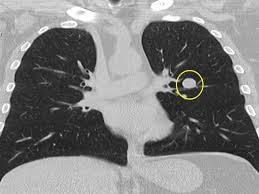

Με τον όρο οζίδιο ή όζος, εννοούμε ένα υπέρπυκνο ιστό σε σχέση με το υπόλοιπο πνευμονικό παρέγχυμα το οποίο εντοπίζουμε με κάποια απεικονιστική εξέταση όπως ακτινογραφία ή αξονική τομογραφία θώρακος.

Ένας όζος παρατηρείται τυχαία κάθε 500 περίπου ακτινογραφίες θώρακος. Μπορεί να είναι ένας οπότε ονομάζεται μονήρης όζος ή πολλαπλοί.

Είναι πολύ σημαντικό να επιβεβαιωθεί αν ένα οζίδιο είναι καλοήθες ή είναι σε πολύ αρχικό στάδιο κακοήθεια.